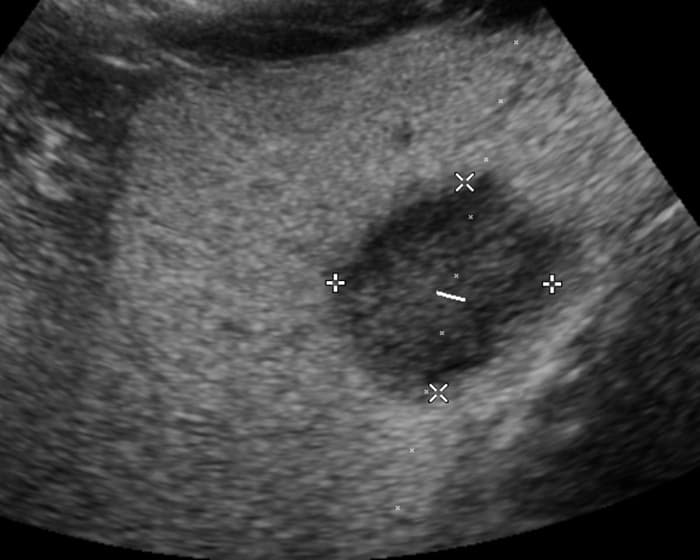

Ung thư đường mật

» Thông tin: Nam giới – 57 tuổi.

» Lâm sàng: Đau bụng.